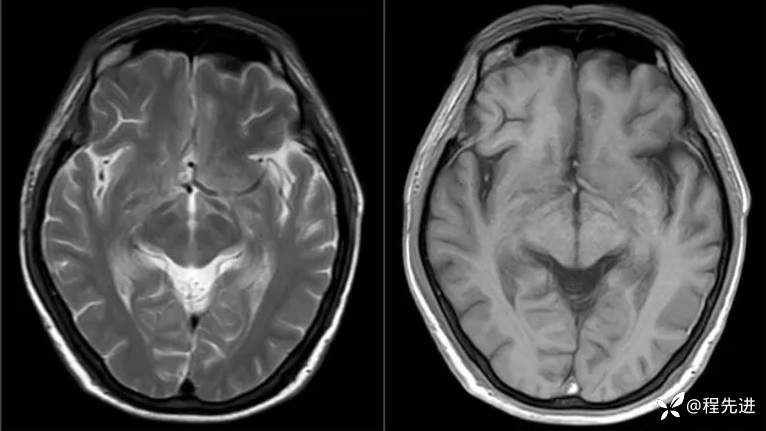

MRI平扫+增强:

T2、T1: